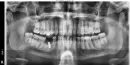

1,5 года назад поставил имплант в клинике "N". Спустя примерно год собрался его протезировать в другой клинике, так как переехал жить в другой город. Там мне сказали, что для данного места поставленный имплант очень маленький. Зуб не будет на нем держаться, так как вкручен он неверно, криво.

Что мне делать с зубом? Могу ли я вернуть деньги за поставленный имплант в клинике "N"?